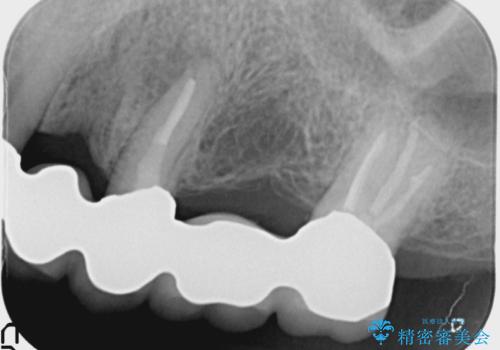

- 左上の歯ぐきが腫れていることを主訴に来院された患者様です。

精査したところ、歯ぐきが腫れている左上の小臼歯(左上4)は保存不可能な状態でした。

保存不可能な歯(左上4)を抜去後、ブリッジによる補綴治療を行いました。